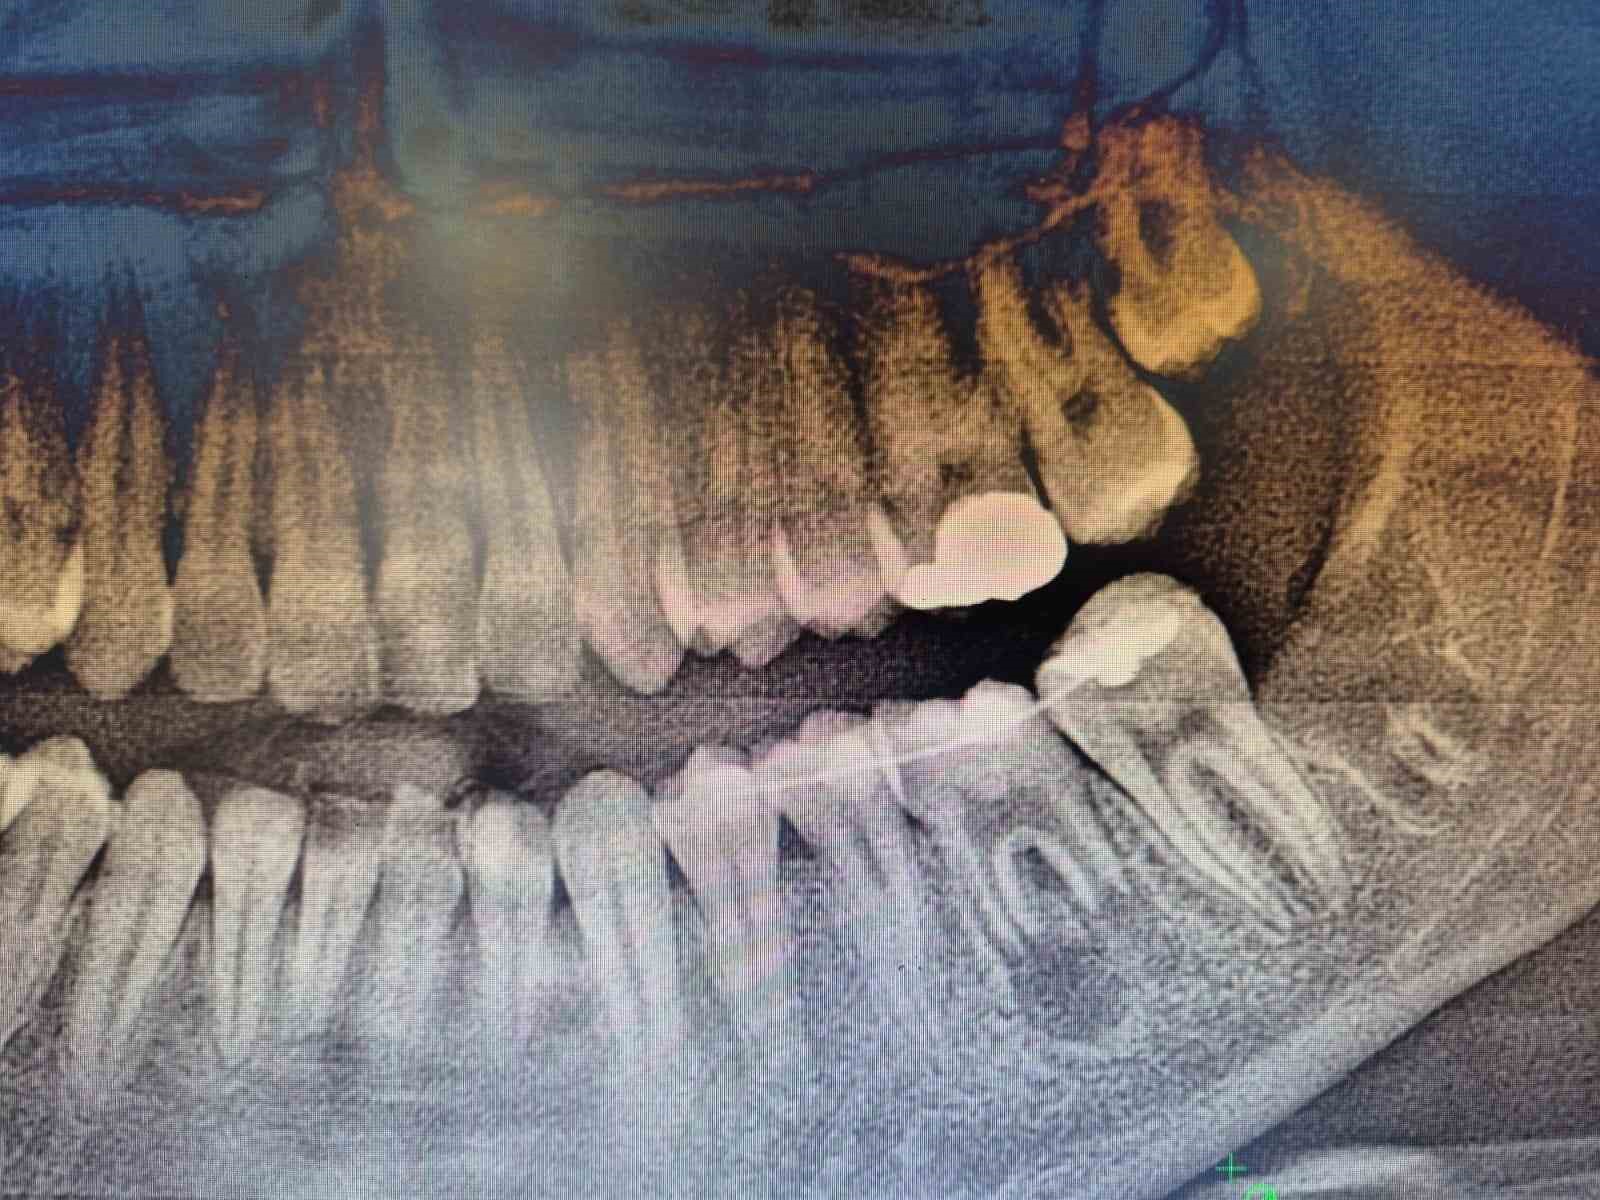

İleri düzey çürük nedeniyle daimi azı dişi çekilen hastaya, yaşı gereği çene gelişimi devam ettiği için klasik implant tedavisi uygun görülmedi. Bunun yerine, hastanın ağzında gömülü halde bulunan yirmi yaş dişi, uzman ekip tarafından cerrahi operasyonla çıkarılarak çekilen dişin yerine nakledildi.

Operasyon sırasında, dişin sağlıklı bir şekilde tutunmasını sağlamak için hastanın kendi kanından elde edilen PRF (Platelet Rich Fibrin) materyali, nakil öncesi hazırlanan diş yuvasına yerleştirildi. Bu uygulama, doku iyileşmesini hızlandıran ve hücre yenilenmesini destekleyen doğal bir yöntem olarak öne çıkıyor. Bu tedavi yöntemi, hastanın kendi dişi kullanıldığı için doğal görünüm, uyum ve fonksiyon açısından büyük avantaj sağlıyor. Aynı zamanda, vücut tarafından kabul edilme oranı yüksek olduğundan, uzun vadeli başarı şansı da oldukça yüksek.